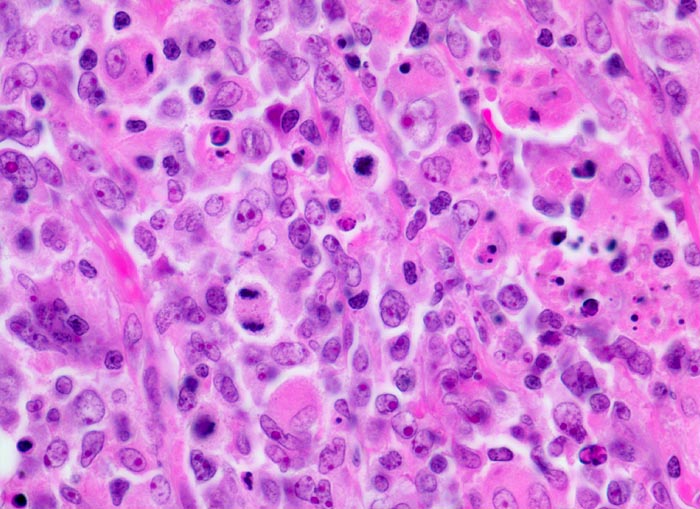

Diffuses grosszelliges B-Zell Lymphom

Mittelgrosse stark polymorphe Tumorzellen mit unregelmässig geformten, teils lobulierten oder eingekerbten Kernen. Oft sind mehrere randständige Nukleolen erkennbar (Zentroblastische Variante). Schmaler Zytoplasmasaum. Zahlreiche Histiozyten mit reichlich eosinophilem Zytoplasma und ovalen Kernen ohne Atypien. Mehrere Mitosen und Apoptosen als Ausdruck der raschen Zellproliferation.

Magenlymphom mit Befall abdominaler Lymphknoten.

Histologie

630